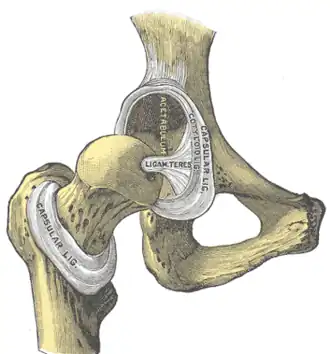

Intracapsular ligament. Left hip joint from within pelvis with the acetabular floor removed (left); right hip joint with capsule removed, anterior aspect (right).

The hip joint is reinforced by four ligaments, of which three are extracapsular and one intracapsular.

The extracapsular ligaments are the iliofemoral, ischiofemoral, and pubofemoral ligaments attached to the bones of the pelvis (the ilium, ischium, and pubis respectively). All three strengthen the capsule and prevent an excessive range of movement in the joint. Of these, the Y-shaped and twisted iliofemoral ligament is the strongest ligament in the human body. It has a tensile strength of 350 kg.[24] Iliofemoral ligament is a thickening of the anterior capsule extending from anterior inferior iliac spine to intertrochanteric line.[7] Ischiofemoral ligament is the thickening of posterior capsule of the hip and pubofemoral ligament is the thickening of the inferior capsule.[7] In the upright position, iliofemoral ligament prevents the trunk from falling backward without the need for muscular activity, thus preventing excessive hyperextension. In the sitting position, it becomes relaxed, thus permitting the pelvis to tilt backward into its sitting position. Ischiofemoral prevents excessive extension and the pubofemoral ligament prevents excess abduction and extension.[26]

The zona orbicularis, which lies like a collar around the most narrow part of the femoral neck, is covered by the other ligaments which partly radiate into it. The zona orbicularis acts like a buttonhole on the femoral head and assists in maintaining the contact in the joint.[24] All three ligaments become taut when the joint is extended - this stabilises the joint, and reduces the energy demand of muscles when standing.[27]

The intracapsular ligament, the ligamentum teres, is attached to a depression in the acetabulum (the acetabular notch) and a depression on the femoral head (the fovea of the head). It is only stretched when the hip is dislocated, and may then prevent further displacement.[24] It is not that important as a ligament but can often be vitally important as a conduit of a small artery to the head of the femur, that is, the foveal artery.[28] This artery is not present in everyone but can become the only blood supply to the bone in the head of the femur when the neck of the femur is fractured or disrupted by injury in childhood.[29]